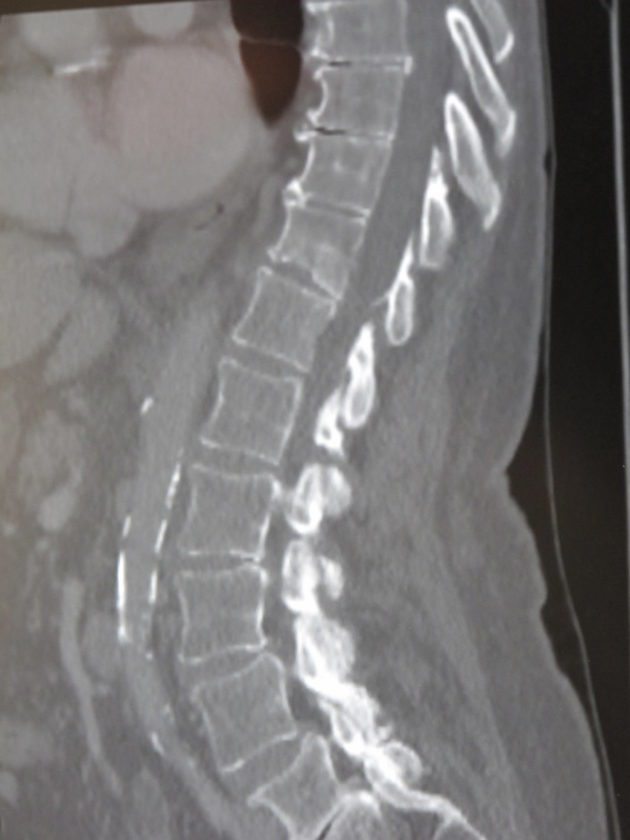

A MRI image of vertebral compression fractures, which were fixed through a vertebroplasty procedure in which bone cement is injected through a small hole into the problem area to relieve back pain. P-J photo by Dennis Phillips

To help relieve the pain for those suffering from chronic back pain, UPMC Chautauqua WCA offers vertebral augmentation procedures like a vertebroplasty. A vertebroplasty is a medical spinal procedures in which bone cement is injected through a small hole in the skin into a fractured vertebra with the goal of relieving back pain caused by vertebral compression fractures.